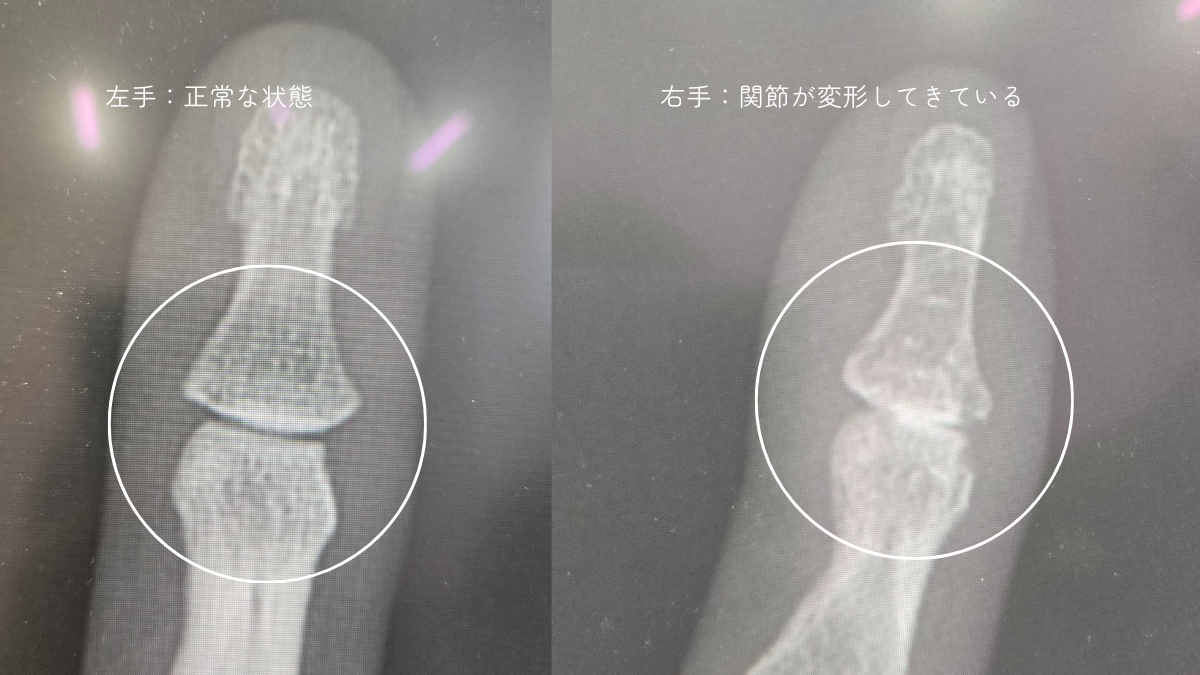

右手の小指の第一関節が”変形している”と言われました。

医師の説明によると、へバーデン結節とは指の第一関節に起こる変形性の関節症。

初期症状としては関節の腫れ・痛み・こわばりなどがあり、進行すると痛みが増して、関節が大きく変形してくるそうです。